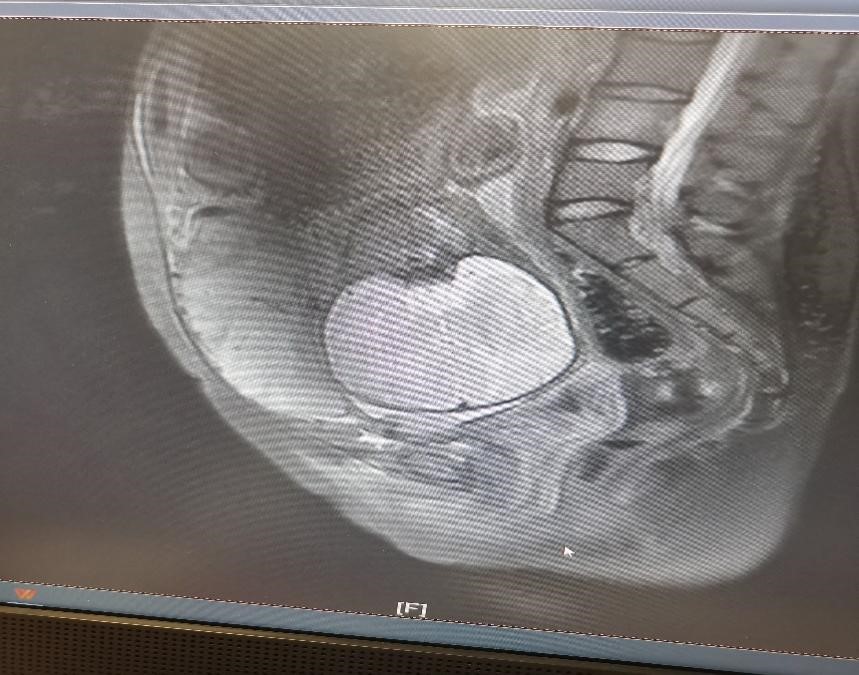

小彭在怀孕早期查B超就提示疤痕部位妊娠可能,医生向患者及家属告知相关风险,但患者及家属继续妊娠意愿强烈。孕14周胎盘完全形成,结合B超结果(胎盘附着在子宫前壁等)和前次剖宫产病史,判断为凶险性前置胎盘(图1)。此时小彭面临困境在于无论是选择终止妊娠还是继续妊娠,出血、切子宫的风险都很大,甚至有危及生命的可能:若选择终止妊娠,可能因出血切除子宫导致无法生育;若选择继续妊娠,分娩时面临的风险同样是大出血切子宫,但能保住孩子,最后经过患者及家属商量后,决定承担风险,继续妊娠。

图1

小彭在孕32+5周时,外院磁共振检查却提示未见胎盘植入,但B超始终提示胎盘内见数个液性回声,前壁峡部肌层内血流信号丰富,磁共振与超声的检查结果似乎不一致,患者及家属辗转苏州多家医院咨询相关风险,一路奔波,最后来到我院找到妇产科张跃明主任。张主任仔细阅读磁共振片子(图2),发现胎盘虽未完全覆盖宫颈内口,但整个胎盘位于子宫下段前壁及前次剖宫产疤痕处,子宫下段前壁肌层缺如,认为此例凶险性前置胎盘情况不可小觑。随后通过B超检查行胎盘植入评分为5分(≤5分为轻度),如果按胎盘植入分判断,可期待至37周终止妊娠即可,所需输血量较少,且无需其他学科参加。但张跃明主任凭借多年丰富的临床经验,结合磁共振图像及B超评价,认为情况远不如看上去一般轻松。目前产妇已孕36+4周,不能继续再期待,应立即收入院。